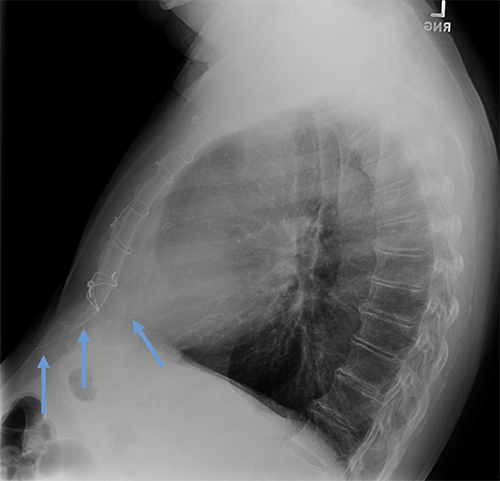

- CEID images with lead types:

Cut epicardial wires (often hard to see)